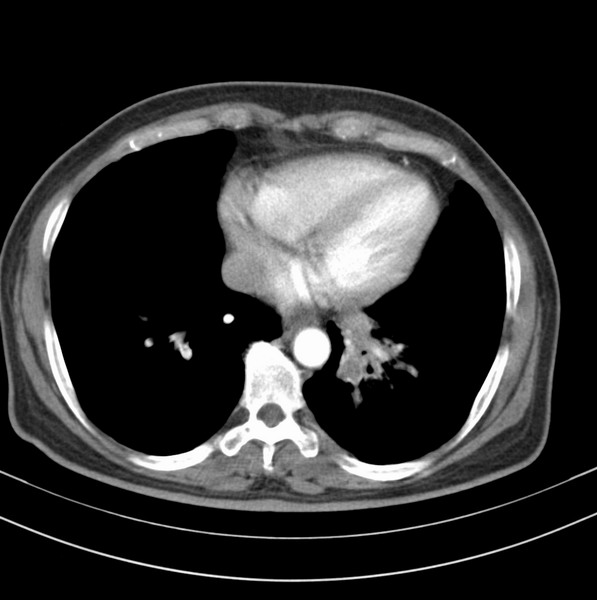

女、63

咳嗽、胸痛四个月

考虑左下肺中央型肺癌

支持左下中央型肺癌伴阻塞性炎症不张。

包绕左下肺基底段的不规则的软组织肿块,段支气管腔变形、狭窄及阻塞性炎症,病变区不规则强化,又是老年女性支持楼上看法。

考虑左肺下叶中央型肺癌伴阻塞性肺炎、支气管黏液嵌塞。

典型病例:左下肺基底段中央型肺癌,相应支气管狭窄并阻塞性炎症